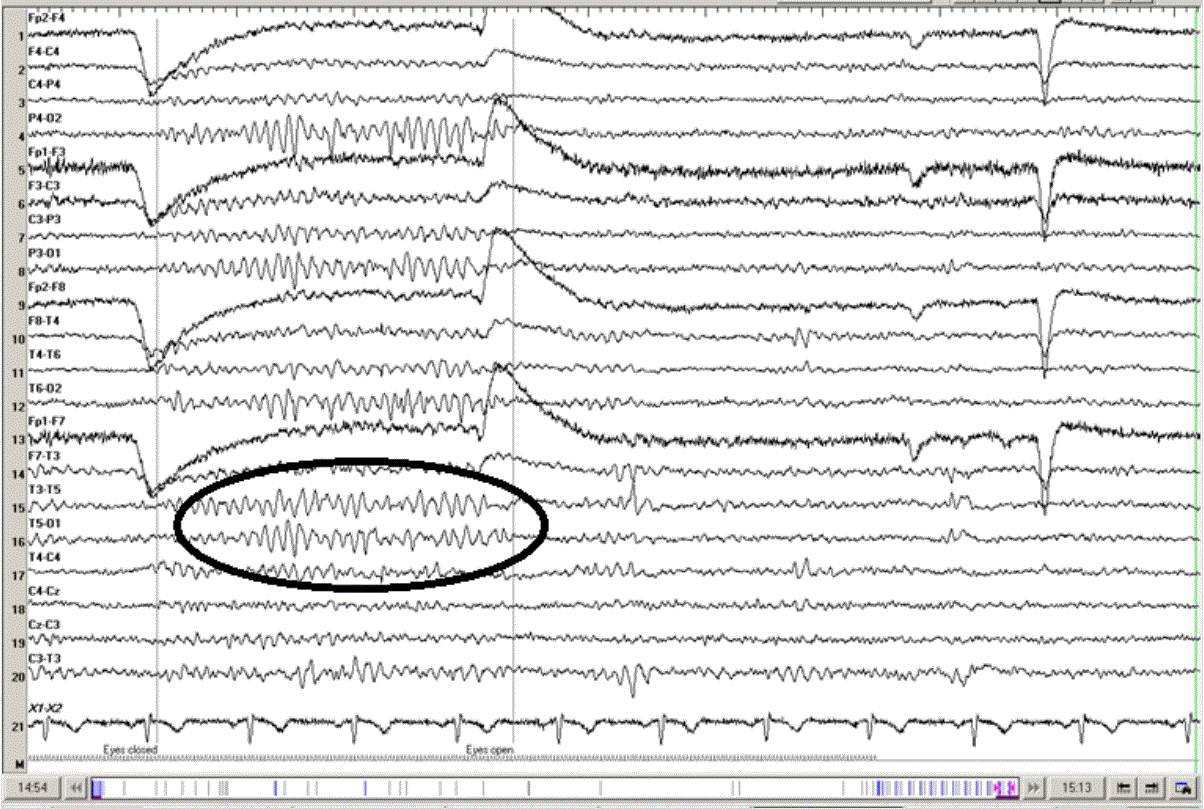

RMTTD (Psychomotor variant)

• Theta

• Midtemporal

• Unilateral/bilateral

• Does not evolve or spread to other sites

• 5-15 seconds duration

• Wake (less during drowsiness and disappears during light NREM sleep) (? Research this)

• Teen/adult